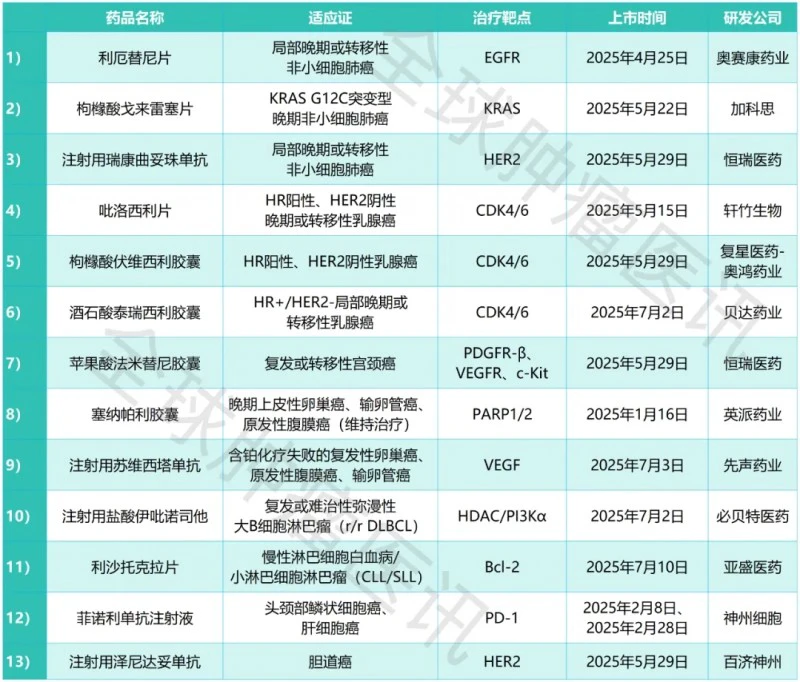

2026年,中国抗肿瘤新药迎来「爆发之年」:15款重磅品种全透视

2026年注定是中国抗肿瘤药物研发史上不平凡的一年。今年预计将有34款抗肿瘤新药首次在国内获批上市,其中15款已被CDE纳入优先审评。从ADC到CAR-T,从双抗到新一代激酶抑制剂,国产与进口创新药同台竞技,正在重塑中国肿瘤治疗的未来图景。